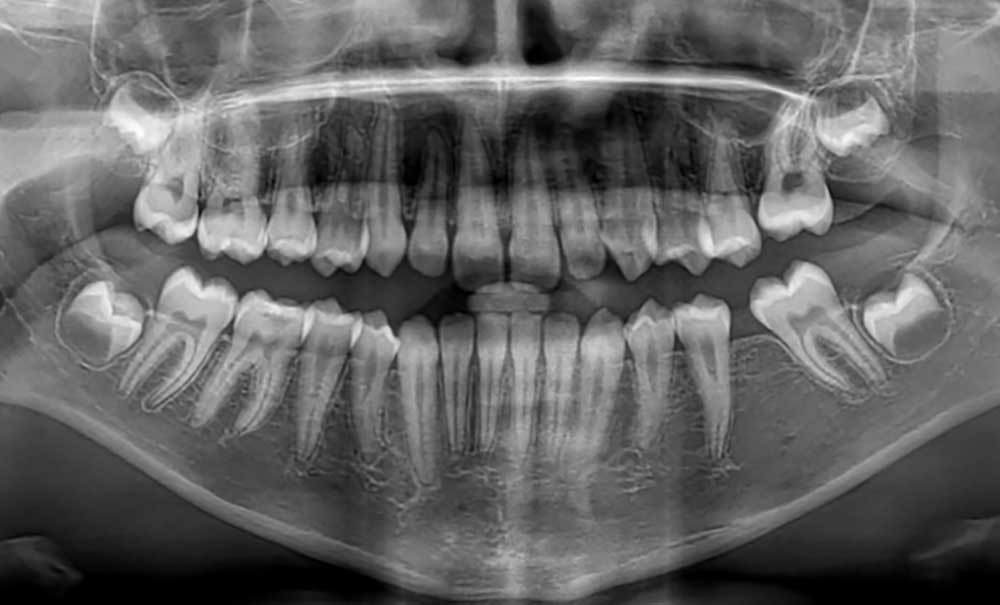

La première molaire permanente (PMP), pilier de l’occlusion, est aussi l’une des dents le plus souvent compromise dès l’enfance. Son délabrement, lié aux caries ou aux anomalies de minéralisation, pose un véritable défi thérapeutique. Entre conservation et extraction, la décision doit être individualisée et s’appuyer sur une approche pluridisciplinaire, guidée notamment par l’âge du patient et le contexte orthodontique.

La première molaire permanente (PMP) délabrée représente un challenge pour le binôme dentiste-orthodontiste. En effet, sa large surface occlusale lui confère un rôle primordial dans la fonction masticatoire. En 1900, Edward Angle la qualifie de « pierre angulaire de l’occlusion », et fonde sa classification sur sa position antéro-postérieure [1]. Avec son antagoniste, elle constitue le couple dentaire offrant la plus grande stabilité occlusale et participe au développement des arcades dentaires. De plus, la PMP joue également un rôle de guide d’éruption pour les prémolaires et les secondes molaires permanentes [1].

L’éruption de la PMP débute vers l’âge de 6 ans et son édification radiculaire s’achève aux alentours de 9-10 ans.